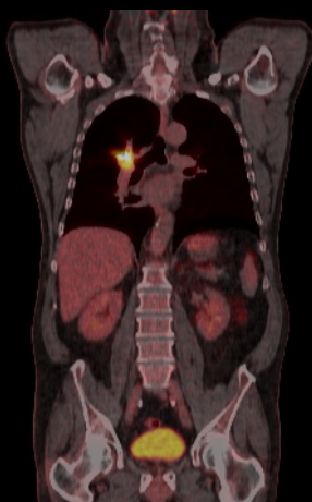

blauer Punkt Plattenepithelkarzinom des rechten Lungenunterlappen cT3 cN3 M1. Der Primärtumor im rechten unteren Hilus und die Mediastinalen Lymphknoten reichern deutlich an. Metastasen in der Wirbelsäule und in 3 Rippen rechts sind erkennbar.